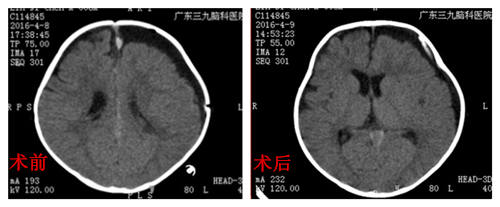

童童,男婴,八个月大,因蛛网膜囊肿入院。据童童的母亲朴女士介绍,在她怀孕33周的一次产检,B超检查发现胎儿颅内蛛网膜囊肿,当时在产科医生的建议下,先把宝宝生下来,定期复查,以密切观察囊肿的变化。童童出生后表现出头颅稍大,为进一步诊治来到广东三九脑科医院小儿神经外科,常规复查头部提示:左侧额颞顶枕部慢性硬膜下血肿,左侧颞部蛛网膜囊肿。入院后积极完善术前相关检查,无手术禁忌症情况下,2016年4月8日在全麻下行“硬膜下血肿钻孔引流术”,术中成功置入2.5#引流管一根,手术顺利。